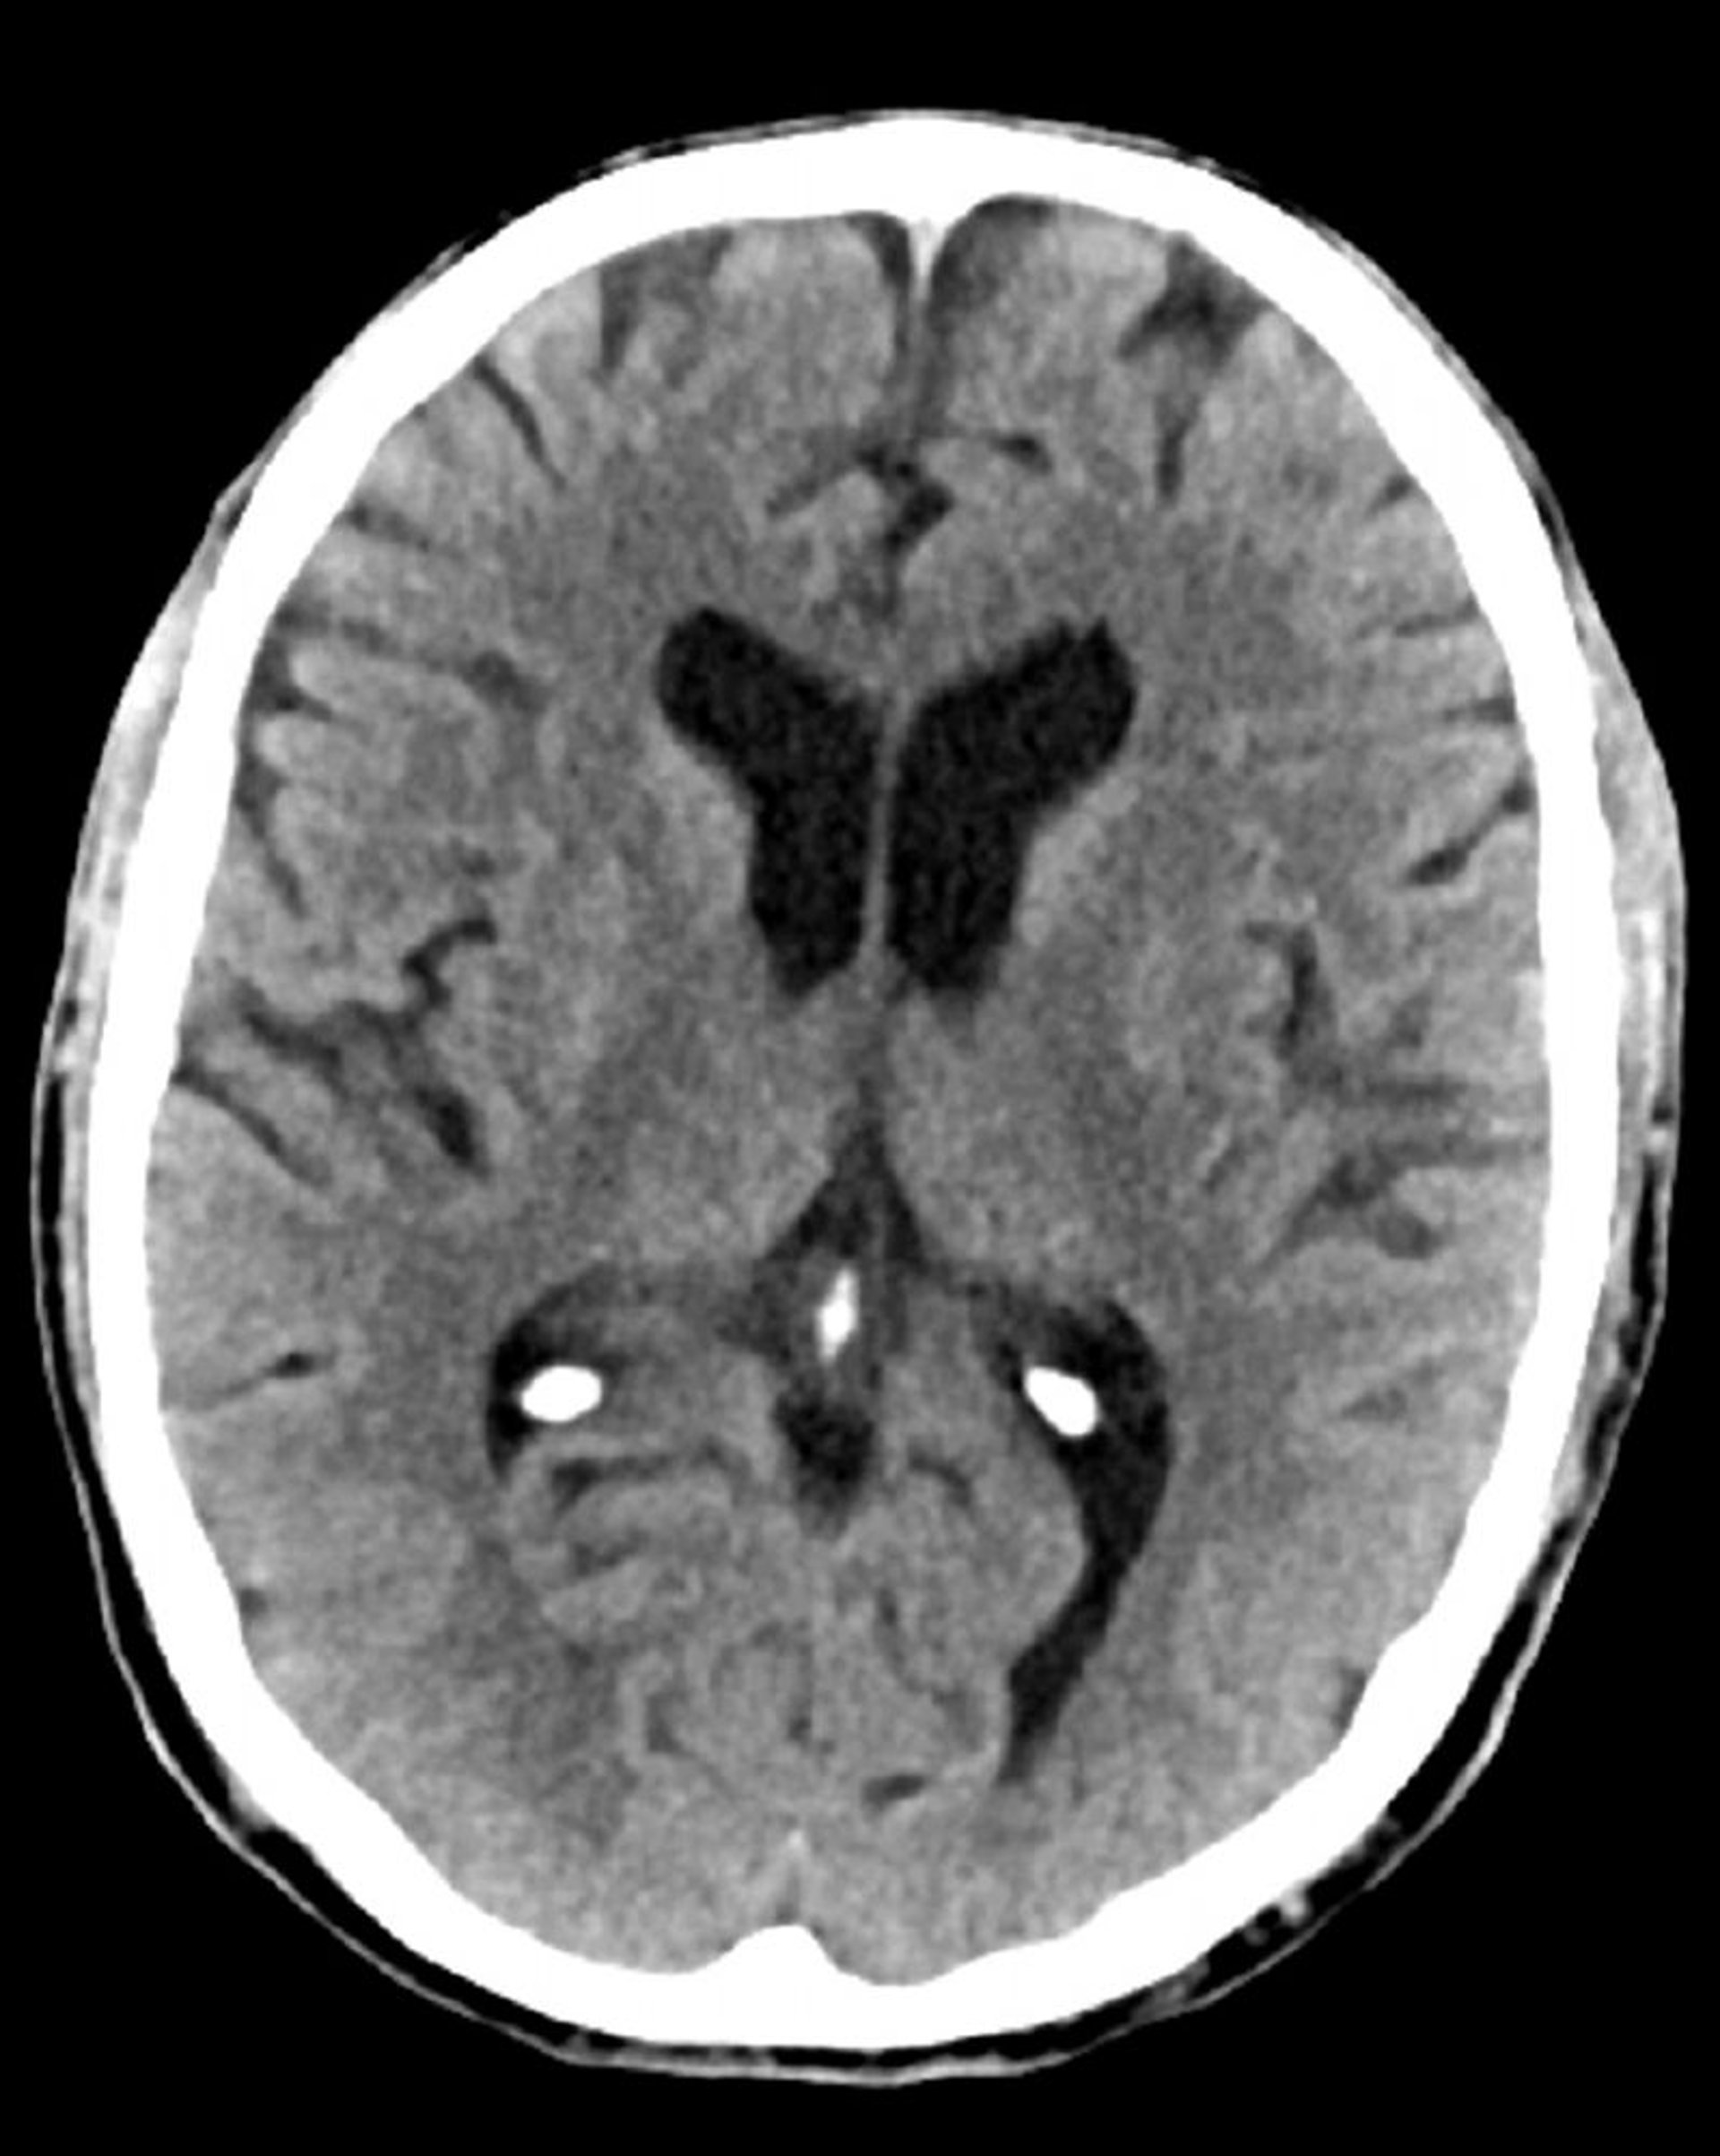

TC de crânio normal (adulto, idade 74) – – Diapositivo 5

Essa é uma TC normal da cabeça de um adulto com 74 anos. Quando comparada com a tomografia computadorizada normal da cabeça da pessoa de 30 anos de idade, os ventrículos e sulcos são maiores. Esses achados são normais nessa faixa etária.